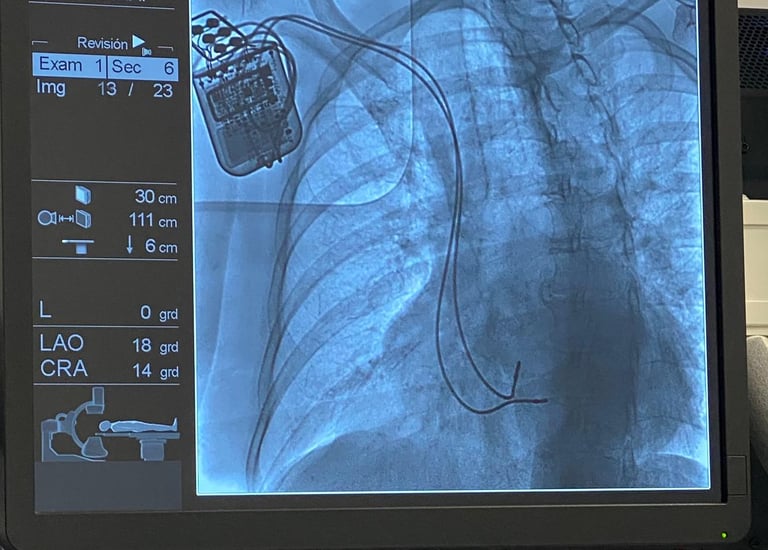

El 2 de Enero del 2024 se realizó el segundo implante de la terapia de modulación de la contractilidad cardiaca a cargo del Doctor Ulises Rojel Martínez en la Ciudad de Puebla